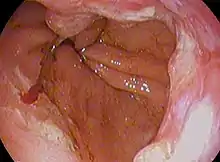

Esophageal cancer (lower part) as a result of Barrettʼs esophagus

The long-term erosive effects of acid reflux (an extremely common condition, also known as gastroesophageal reflux disease or GERD) have been strongly linked to this type of cancer.[26] Longstanding GERD can induce a change of cell type in the lower portion of the esophagus in response to erosion of its squamous lining.[26] This phenomenon, known as Barrett's esophagus, seems to appear about 20 years later in women than in men, possibly due to hormonal factors.[26] Having symptomatic GERD or bile reflux makes Barrett's esophagus more likely, which in turn raises the risk of further changes that can ultimately lead to adenocarcinoma.[16] The risk of developing adenocarcinoma in the presence of Barrett's esophagus is unclear, and may in the past have been overestimated.[2]